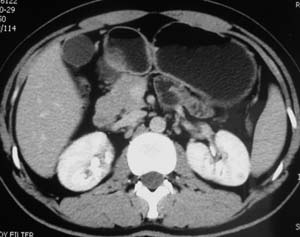

以下是引用子期在2010-3-19 20:47:00的发言:[br]血管畸形的ct增强应该有明显强化,本例并不相符合。本例双肾局部的略低密度影,累及肾盂,局部皮质明显变薄、内陷,增强扫描有轻度的强化,应考虑为炎性病变,患者为年轻男性,累及双肾的感染以结核较常见,可以没有明显的临床症状,尿中有时候也并不能查出什么;肾脓肿常有明显感染中毒症状,本例不符,另外一般的肾盂肾炎或肾小球肾炎通过小便就可确诊,其它还不能排除的是黄色肉芽肿性肾盂肾炎,然而单凭ct一般也很难鉴别。